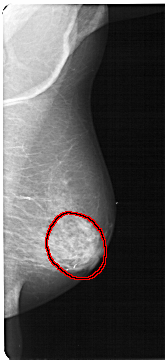

LEFT_MLO LINES 5491 PIXELS_PER_LINE 2416 BITS_PER_PIXEL 12 RESOLUTION 43.5 OVERLAY

FILE: A_1302_1.LEFT_MLO.OVERLAY

TOTAL_ABNORMALITIES 1

ABNORMALITY 1

LESION_TYPE CALCIFICATION TYPE PUNCTATE-AMORPHOUS DISTRIBUTION REGIONAL

ASSESSMENT 4

SUBTLETY 3

PATHOLOGY BENIGN

TOTAL_OUTLINES 1

BOUNDARY